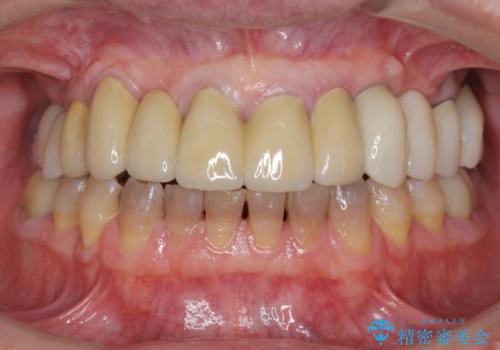

- 他院で上顎は全て抜歯し、入れ歯にする必要があると言われ相談に来院されました。

検査の結果、重度の歯周病であることから保存が難しい歯は抜歯を行いインプラントを、残すことが可能な歯には再生治療を含めた歯周病治療を行いより多くの歯を残す歯周病治療を計画します。

上顎は、残っている前歯も揺れがあり残すためにはクラウンでつなぐ歯周補綴が必要な状態です。

また咬合負担に不安のある前歯を助けるためにも、臼歯部にインプラント補綴を行いしっかりとかめる状態とすることも大切です。